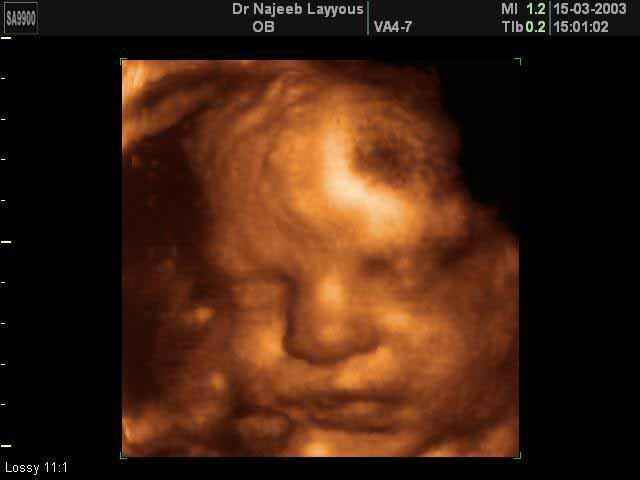

- Fetal Face Ultrasound Photos

- 3D Fetal Profile Ultrasound Scan Photos

- The Clinical Advantages of 3D and 4D Ultrasound

- Definition and Features of Four Dimensional Ultrasound

- Uses of 4D Ultrasound scan

- The importance of 4D ultrasound imaging in pregnancy